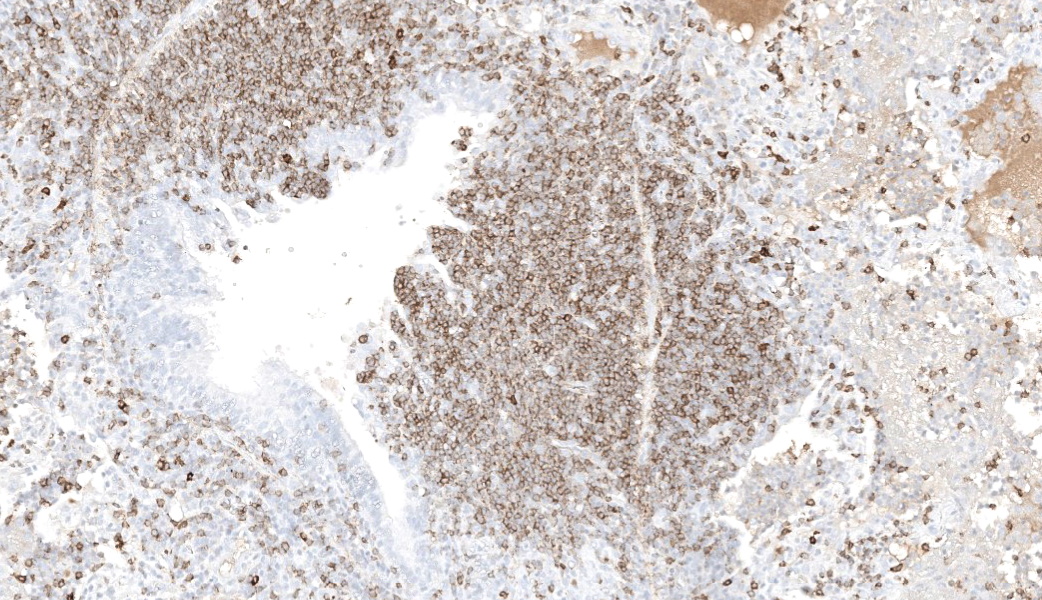

Immunohistochemical markers

|

Marker |

Cell type |

Tissue |

Number of positive cells |

Positive cell distribution |

CD79b |

B Cell |

Lung |

+++ |

Majority of cells within neoplastic infiltrate, scattered cells within peribronchial and peribronchiolar spaces, interlobular and alveolar septae and alveolar lumen |

Lymph node |

The majority of cells within the cortex and moderate numbers (30-50% of cells) within the medulla |

||

Spleen |

Majority of cells within red and white pulp |

CD3 |

T Cell |

+ |

Scattered throughout parenchyma, and small numbers accompanying neoplastic infiltrate |

++ |

Moderate numbers multifocally throughout the medulla |

Predominantly around blood vessels |

Microscopic Description:

Camel; LungDescription Multifocally throughout the section, expanding the lamina propria of larger airways, multifocally invading the airway epithelium, expanding numerous alveolar septae and infiltrating into interlobular septae and the pleural space, there is a densely cellular lymphoid neoplasm. The neoplasm is made up of sheets and rows of closely packed round cells supported by a fine pre-existing fibrous stroma. The neoplastic cells contain nuclei 5-7µm in diameter and have indistinct cytoplasmic borders, scant amphophilic cytoplasm, round to ovoid paracentral nuclei with coarsely clumped chromatin with moderate numbers of cells possessing a single nucleolus. Throughout the neoplastic cells there is mild anisokaryosis and anisocytosis. Mitotic figures numbering 5 per 2.37mm2 with occasional bizarre mitoses. Multifocally the neoplastic cells closely surround and infiltrate the tunica media of small blood vessels. Numerous alveolar spaces are filled with eosinophilic fibrillar material (fibrin) admixed with abundant neutrophils and foamy macrophages, while others contain large amounts of homogenous eosinophilic material (edema). Multifocally some alveolar spaces are expanded and ruptured (emphysema). Bronchioles contain moderate numbers of neutrophils and macrophages admixed with strands of hypereosinophilic fibrillar material (fibrin) with neutrophils transmigrating across the respiratory epithelium. There is occasional loss of type I pneumocytes with replacement by type II pneumocytes.

Camel; Paratracheal Lymph NodeDescription Multifocally the normal architecture of the cortex, paracortex and medulla is disrupted and replaced by a densely cellular neoplasm composed of lymphoid cells. The neoplasm is comprised of sheets of closely packed small round cells with nuclei 5-7µm in diameter. Cells are mostly round with indistinct cytoplasmic margins, scant basophilic or eosinophilic cytoplasm, high nuclear to cytoplasmic ratio, and a paracentric nucleus with coarsely clumped chromatin. There is mild anisocytosis and anisokaryosis. There is an average of 12 mitoses per 2.37mm2. Within the capsule of the lymph node there are small aggregates of neoplastic cells organized into sheets.

In this case, neoplastic cells were also found in the liver, spleen and heart of the camel. No neoplastic cells were found in the kidneys or in two sections of bone marrow (rib and sternum). The presence of atypical lymphocytes within the peripheral blood collected at the initial clinical examination greatly aided the diagnosis of lymphoma or leukemia in this case (Figure 1) and allowed the clinician to understand why this animal did not improve like the others in the herd once nutrition was improved. The neoplastic cells observed in the peripheral blood was suspected to be secondary to the lymphoma, given that no neoplastic cells were found within the bone marrow of the bones examined histopathologically. Leukemia is a feature of less than 20% of lymphomas in animals and is more commonly a feature of T-cell lymphomas.9 Leukemia is most likely observed when the lymphoma invades the bone marrow or spleen, the latter of which contained neoplastic cells in this case.9 In this case a B-cell phenotype was confirmed via immunohistochemistry (Figures 7-11).There are only a few reports in the literature describing lymphoma in dromedary camels. Similar to this case, the disease is typically reported in adult animals (>7 years) and has been reported in both male and female camels. Common clinical presentations include weight loss, anorexia, polyuria and polydipsia, with one report also describing peripheral lymphadenopathy and bilateral masses in the conjunctiva of one animal.3,4,6 Peripheral lymphocytosis, sometimes with significant atypia in circulating lymphocytes and lymphoblasts, has been reported occasionally but is not always a feature of the disease in dromedary camls.3,7

In contrast to this case, all cases in the literature from dromedary camels were identified as T-cell lymphomas. In those cases, lymphocyte lineage identification was performed using immunohistochemistry and identified the neoplastic cells as CD3 (pan T-cell) positive and either CD20 or CD79a (pan B-cell markers) negative.3,4 More recently, flow cytometry has been used to further classify a multicentric T-cell lymphoma as a gd T-cell lymphoma and a combination of CD4 and WC-1 markers.4 Other markers which have been used in the literature to differentiate round cell neoplasms in camelids include PAX-5, CD79b (B-cell markers), CD5 (T-cell marker), MUM1 (plasma cell marker), CD18 and CD68 (histiocyte markers).1,4,6,8